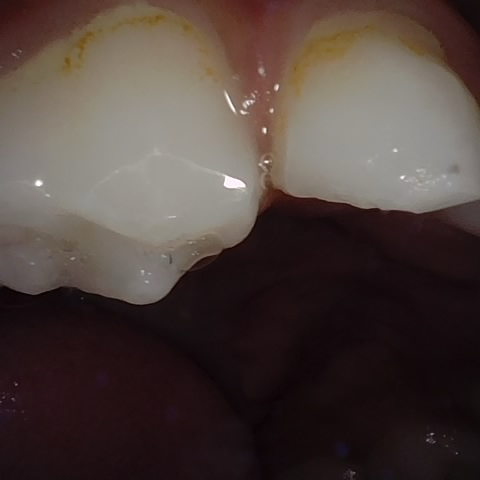

NHD31075

Annotated as "Good"